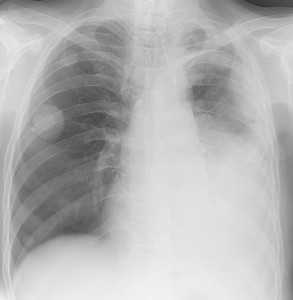

Метастазы в легких — фото рентгенограммы. Округлые тени — метастазы рака пищевода. Хорошо виден большой узел округлой формы вблизи переднего отрезка 2-го ребра. На снимке справа - циркулярное сужение пищевода за счет опухолевого утолщения его слизистой оболочки.

Как выглядят метастазы в легких на рентгене? Слева — узловые образования у пациента с раком яичка. Справа - метастазы рака яичников гематогенного характера с выраженным опухолевым лимфангиитом (обратите внимание на деформированный сетчатый, линейный характер легочного рисунка).